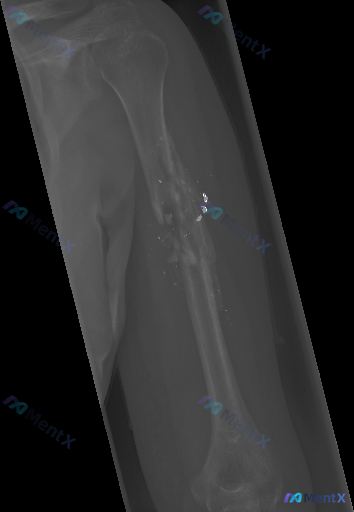

- 骨骼:肱骨干中段可见明确的皮质连续性中断,呈粉碎性骨折表现,有多个游离骨碎片,骨干轴线明显错位,局部还有骨质缺失,骨折边缘看起来不太规则。

- 骨密度/纹理:骨折端周围骨密度不均,部分区域骨小梁模糊、中断。

- 软组织:骨折周围软组织肿胀明显,密度不均。

- 额外征象:在骨折断端及其周围软组织里,能看到多枚散在的高亮斑点状高密度影。